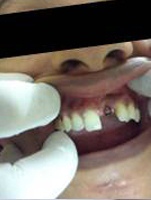

Pre Operation

Single Tooth Implant